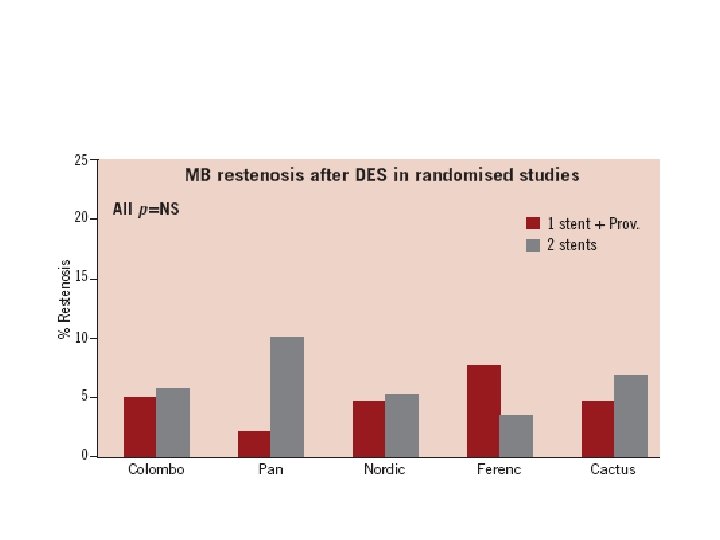

One vs two stents • • • Important trials NORDIC 2 BBC CACTUS

1. Nordic I: provisional T stenting as good as systematic side branch stenting 2. Nordic II: Culotte better than Crush 3. Cactus: provisional T stenting not worse than crush 4. BBC ONE: step wise approach with provisional T stenting better than initial complex procedures 5. Bad Krozingen: no difference provisional vs systematic T 6. Double Kiss Crush Study: DK Crush better than conv. crush Steigen Circulation 2006; 114: 1955; Erglis TCT 2008; Hildick-Smith TCT 200 Ferenc EHJ 2009; Chen JInterv Cardiol 2009; 22: 121 -27